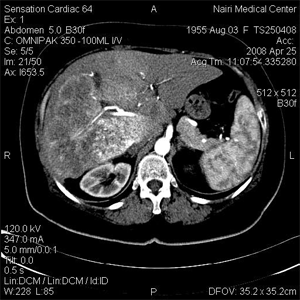

Большие ГЦР экспансивного типа имели четкие контуры, наблюдалось инкапсулирование и внутренняя мозаичная структура. Опухоли инфильтративно- го типа были часто сегментарные, гетерогенные и нечетко очерчены. Диффузный тип ГЦК наименее частый и проявлялся многочисленными мелкими узелками, рассеянными по печени. Более крупные гиперваскулярные опухоли часто были гетерогенными вседствие некроза и кровоизлияний (рис.1). При многослойной СКТ можно было обнаружить мелкие гиперваскулярные узелки. Гиповаскулярные узелки обнаруживались нередко и обычно представляли собой раннюю стадию, они лучше всего были видны без в/в контрастирования и не усиливались или слабо усиливались в артериальной фазе.

Рис.1 Гетерогенная ГЦК с участками некроза и кровоизлияний в нативной фазе